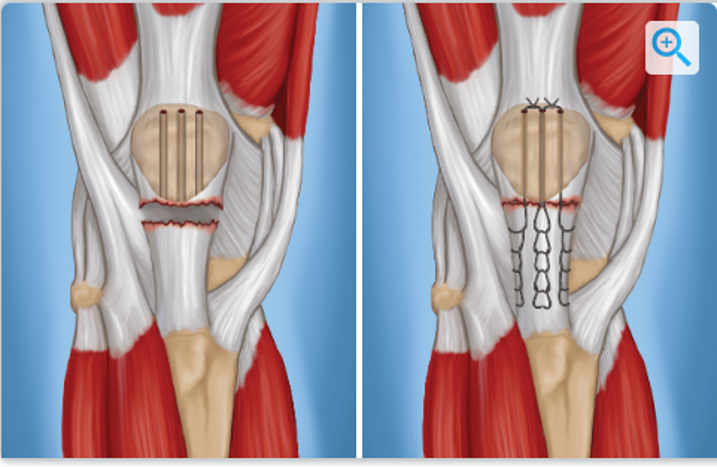

Q

Knee: Patellar Tendon Rupture/ Quad Rupture

PE and Tests

A

Treatment:

Immobilization in KI

Conservative tx w/ intact extensor mechanism

Operative: surgical repair of tendon – suture anchor, end to end, graft

Pearls:

Quad more often in over 40 y.o. patients

Patellar more often in under 40 y.o. patients (30-40yo)

Complications: knee stiffness/re-tear